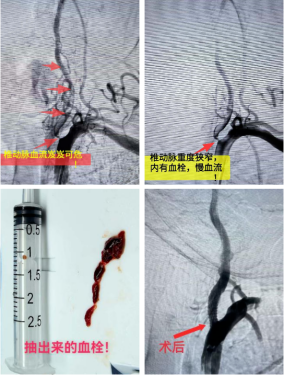

团队当机立断,决定打破常规,立即为患者进行紧急脑血管造影。结果证实了超声的判断:左侧椎动脉起始部重度狭窄,伴活动性血栓,随时有血栓脱落风险;右侧椎动脉纤细,未给颅内供血。患者大脑后循环(负责小脑、脑干等核心区域供血)的“生命线”命悬一线。

明确诊断后,神经疾病综合诊疗中心介入团队迅速为患者实施了“椎动脉取栓术+支架成形术”。

穿刺入路:医生在患者大腿根部的股动脉做一个毫米级的小切口,通过穿刺针建立通往血管的“通道”;

导管导航:将纤细的导管沿着血管通路,在DSA(数字减影血管造影)设备的实时引导下,精准送达椎动脉起始部;

血栓清除:通过导管送入取栓支架或抽吸装置,支架张开后可牢牢“抓住”血栓,再通过缓慢回撤导管将血栓完整取出,或直接用抽吸设备将血栓吸出;

血管再通:血栓清除后,椎动脉血流恢复通畅,基底动脉的供血安全得到保障,从根源上避免了栓塞的发生。

整个手术无需开颅,创伤小、恢复快,在最短时间内解除了血管梗阻,为患者争取了最佳治疗时机,最大限度减少脑组织损伤。

术后,患者头晕症状即刻得到显著改善,致命风险得以解除。如今,患者已顺利出院。